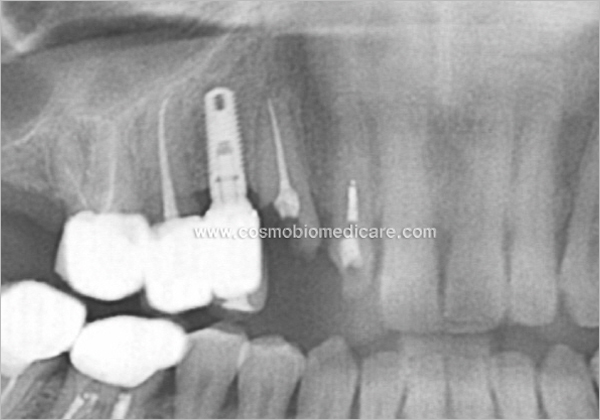

Clinical Cases

• Case1

• Case2

• Case3

• Case4

• Case5

• Case6

• Case7

• Case8

• Case9

• Case10